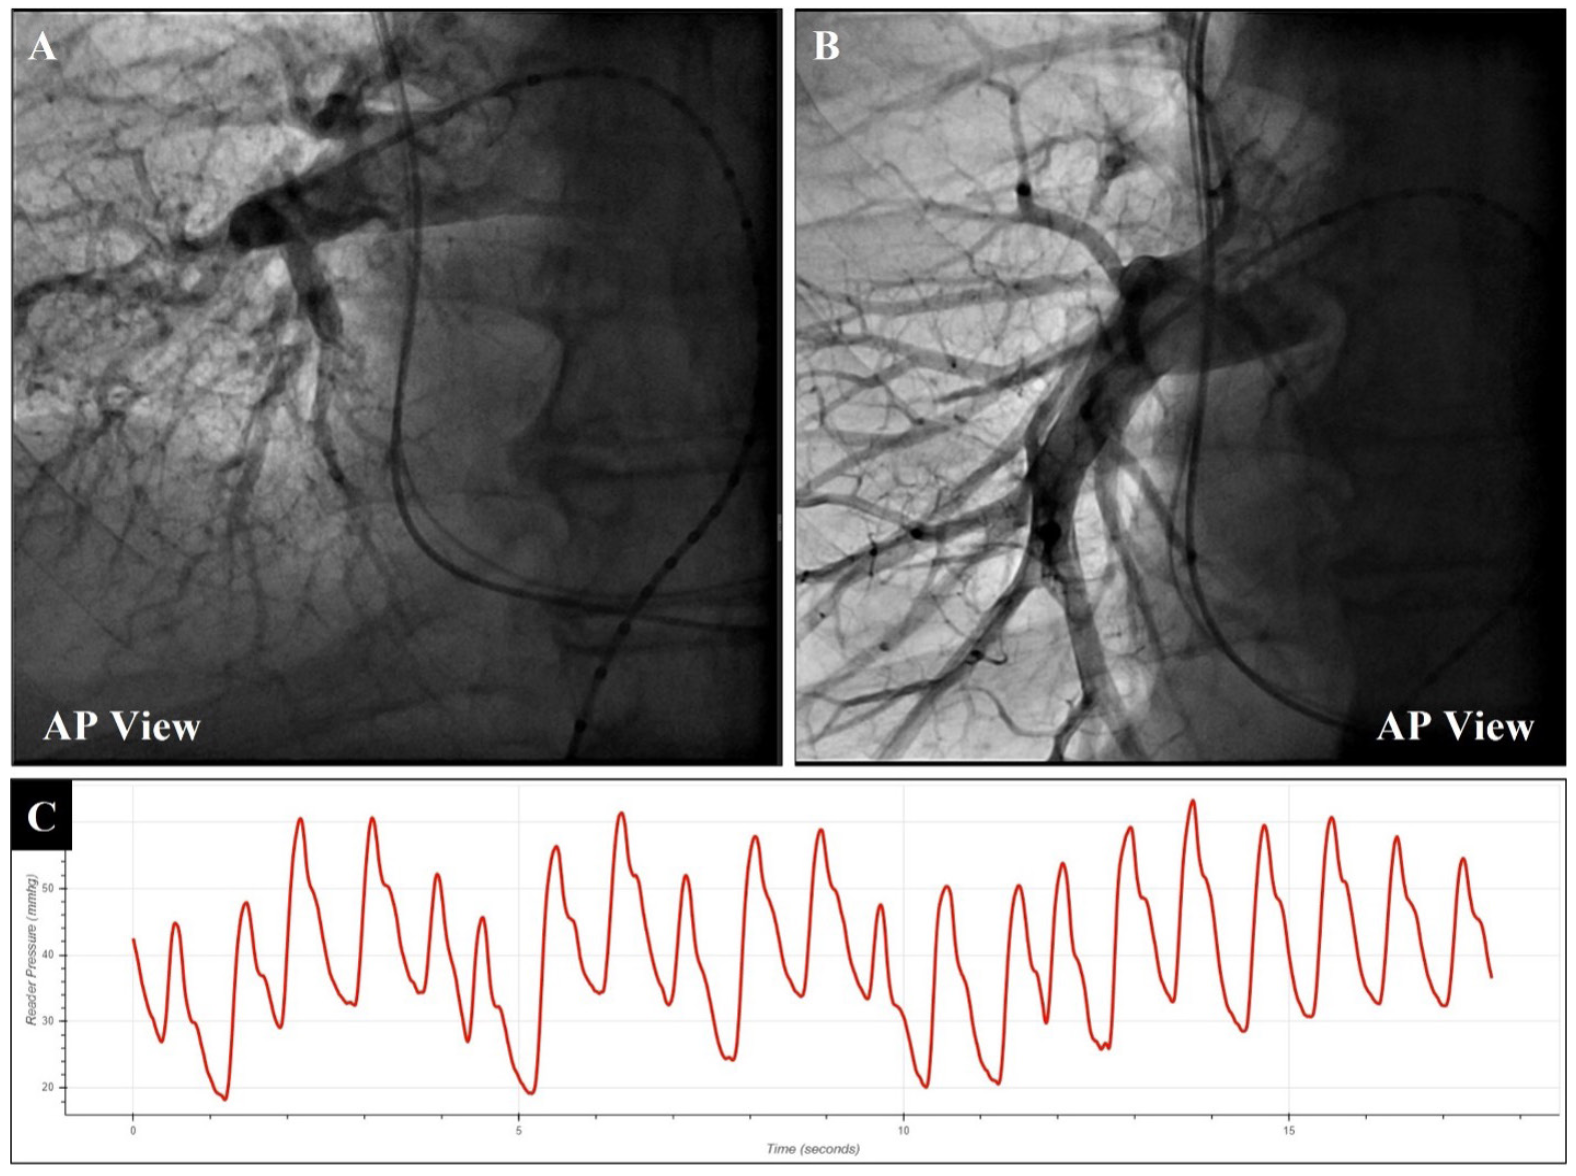

Case 2. A 73-year-old male patient with a history of hypertension, coronary artery disease with previous percutaneous coronary intervention, AF, atrioventricular node ablation with pacemaker implant, and multiple cardiovascular hospitalizations was referred for Cordella implantation. The procedure began with 14-Fr introducer to the right femoral vein, followed by the insertion of the PA catheter for RPA access and assessment of baseline hemodynamics. Using a 0.025˝ Amplatz guidewire, the PA catheter was then exchanged for a straight-flush catheter. The initial AP angiography was done using 2-second power injector (10 mL/sec) with free breathing. On this occasion, identification of the downturn and distal mean RPA vessel was difficult and unclear, as the anatomy of the PA was compressed with the diaphragm elevated. Subsequently, the patient was asked to take a deep breath hold during the angiography. As a result, full inspiration lowered the diaphragm in a way that considerably extended the pulmonary vasculature, reducing the vessel tortuosity (Figure 6A and Figure 6B). This led to the clear identification of the downturn and distal RPA vessels, required to identify the target zone and the ideal pathway for the guidewire. Similarly, angiography was taken in LAO caudal with a deep breath hold. The straight-flush and simplified anatomical structure in the deep breath hold configuration assisted with a straightforward pathway to navigate the guidewire in the A9 vessel. With the Amplatz wire in position, the delivery system was advanced to the target zone over the wire. Periodic full inspiration was applied during this implant for better orientation against the roadmap taken under deep breath hold. The soft tip of the delivery system was well positioned in the distal RPA. After checking the marker bands for correct sensor body orientation, the sensor deployed under deep breath hold successfully on the anterior vessel wall. The torque catheter and Amplatz wire were removed and the sensor was calibrated via the stability sheath. The patient underwent training of the system 3 hours after sensor deployment and was discharged home. Figure 6C highlights the significant respiratory variation that was seen for this particular patient.

This case demonstrated the benefit of deep breath hold to identify the anatomical landmarks that assist during sensor implantation, especially for patients with considerable respiratory variation in their PA hemodynamics. The implantation of the Cordella sensor is landmark based and the roadmap with full inspiration led to a level of consistency with anatomy for determining target guidewire location and sensor target zone. Once a landmark angiogram is made with deep breath hold, it remains beneficial to periodically use breath hold when navigating the sensor to the target zone, as well as during sensor deployment to guarantee ideal anatomical orientation assisted by the roadmap. Therefore, deep breath hold is considered an important part of the implantation strategy for the Cordella sensor.